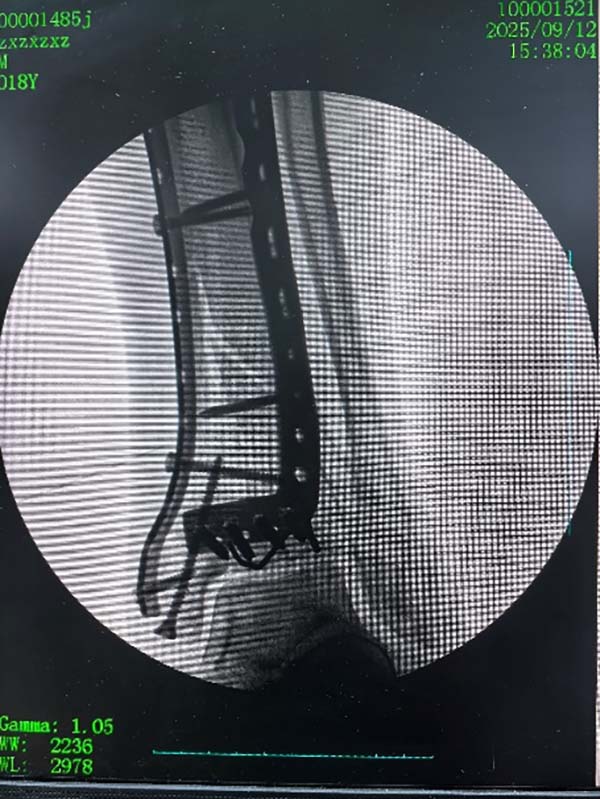

该款机器人适用于关节内骨折的撬拨复位及穿针定位,能够有效帮助医生对关节内复杂的骨折进行毫米级的定位、复位、固定操作。并能够结合前提课题完成的骨折AI识别规划软件,对骨折块进行撬拨复位。目前已在南阳市中医院开展临床研究三十余例。

两款联合使用复位复杂的Pilon骨折: